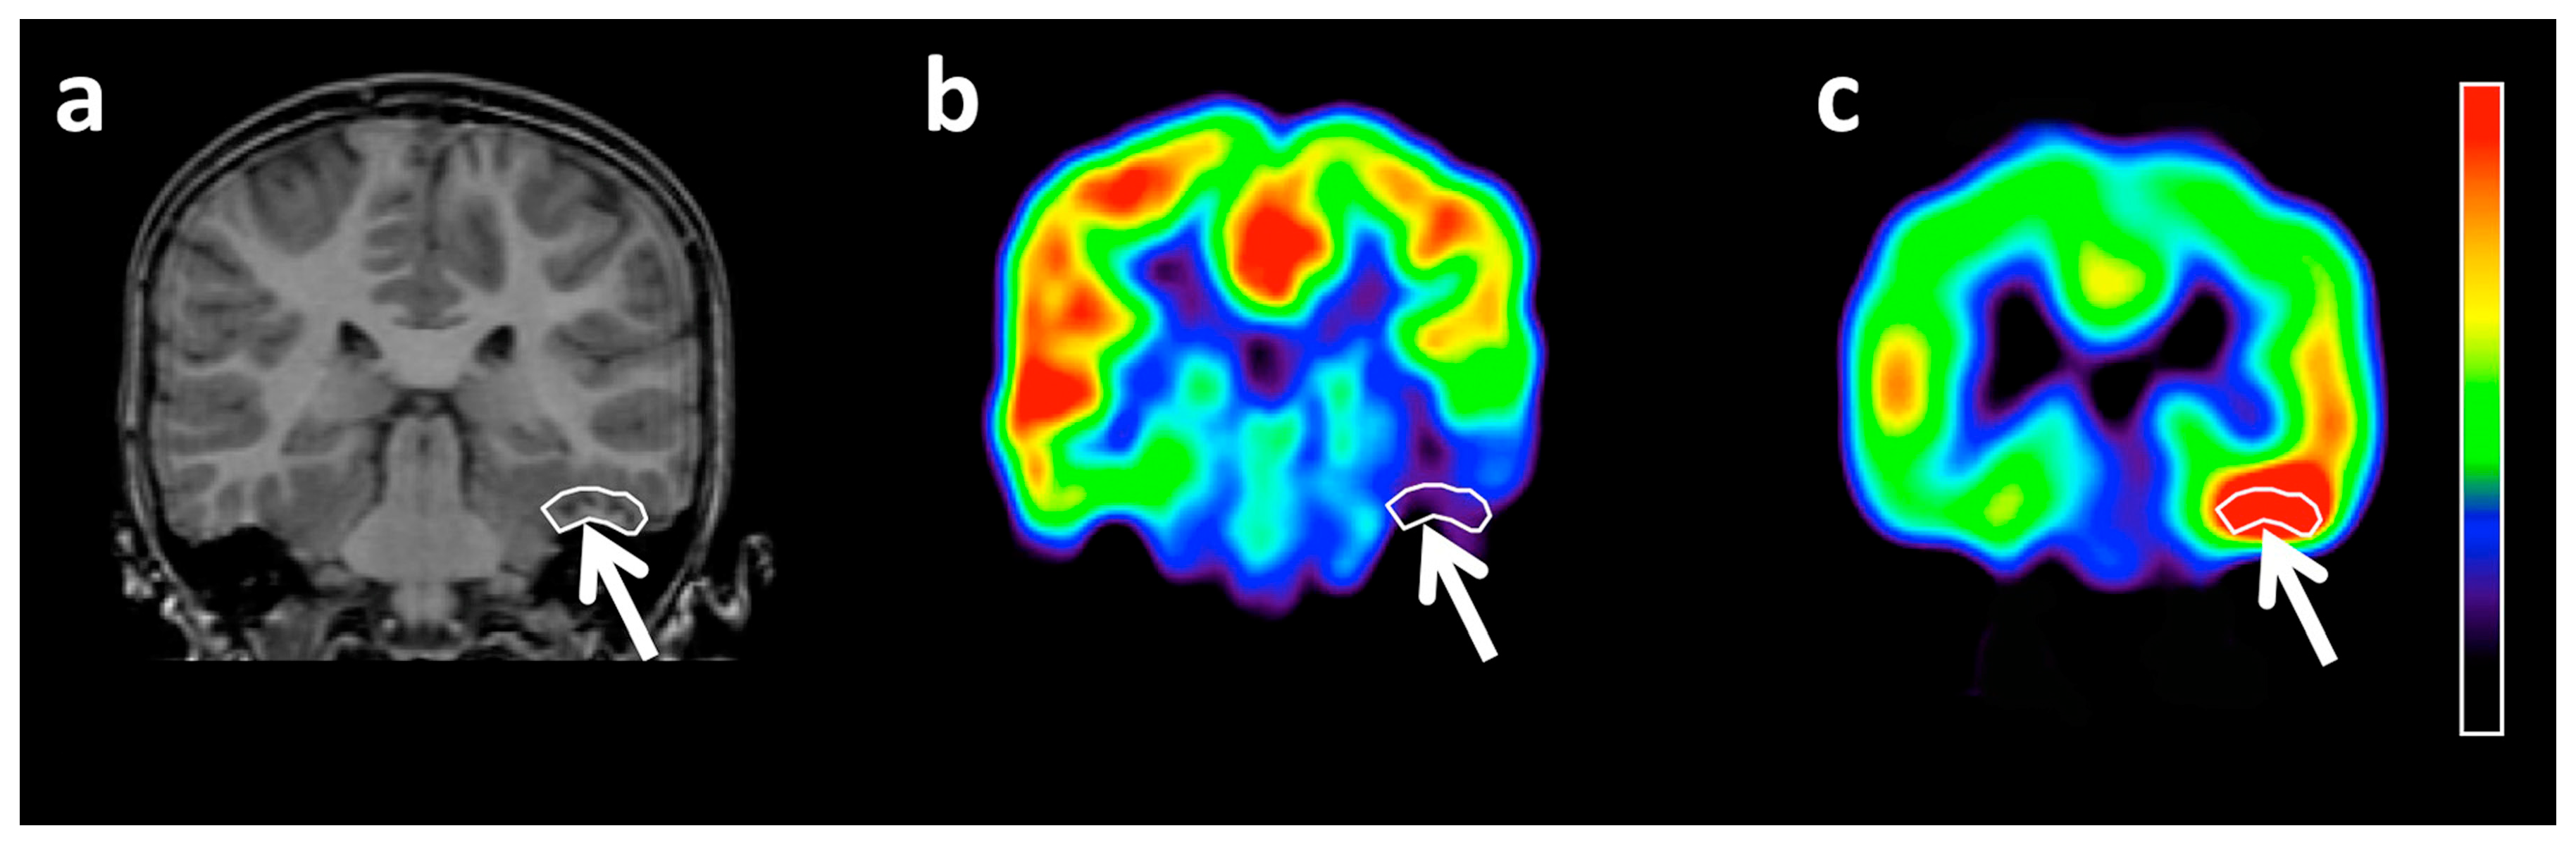

Diagnostics Free Full Text Molecular Imaging Of Brain Tumor

https://www.mdpi.com/diagnostics/diagnostics-10-01049/article_deploy/html/images/diagnostics-10-01049-g001.png